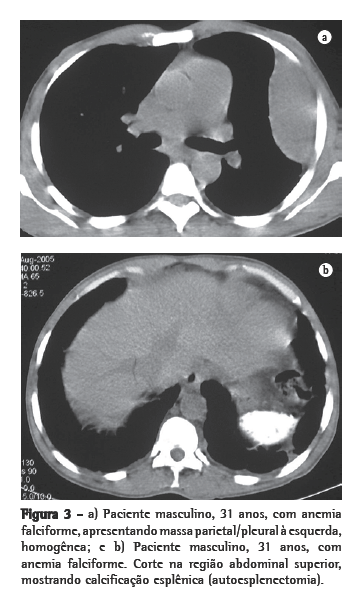

Os outros dois pacientes mostravam massa parietal e pleural, ambas à esquerda, sem evidência de comprometimento paravertebral. Em um desses, a massa era homogênea (Figuras 3a e b); no outro, havia reação óssea associada.

Como achados associados, dois pacientes mostravam calcificações no baço (Figura 4). Ambos eram portadores de anemia falciforme. Dos seis pacientes, dois haviam sido esplenectomizados, e em dois a imagem do baço era normal. Alterações ósseas relacionadas à doença de base foram identificadas em três pacientes.

Todos esses aspectos foram identificados em nossos casos. É interessante ressaltar que os achados em dois pacientes mostravam calcificações no baço, decorrentes de infartos múltiplos, com autoesplenectomia. Ambos eram portadores de anemia falciforme. Esse achado pode também auxiliar no diagnóstico diferencial.